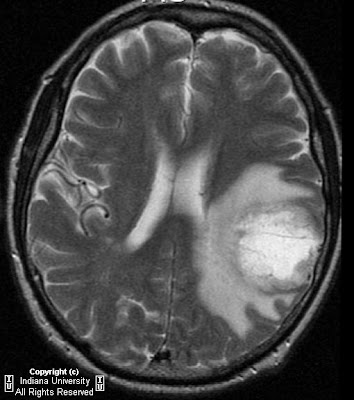

Imaging In Glioblastoma Multiforme: Diagnosis, Treatment, And ...

Imaging in Glioblastoma Multiforme: Diagnosis, Treatment, and Follow-Up Kimberley Mak , HMS III Symptoms Localizing signs such as focal neurologic deficits, seizures, Atkinson DS, Brat DJ. Best cases from the AFIP: glioblastoma multiforme . RadioGraphics 2007; 27:883 -888. 3) ... View Doc